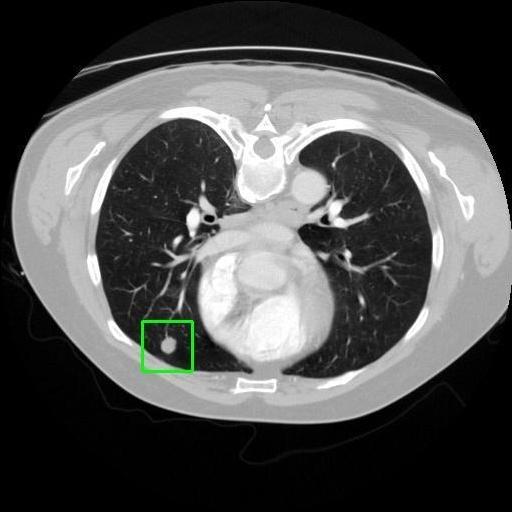

We developed an AI-based system using deep learning models for analyzing lung CT scans to detect and classify pulmonary nodules. We chose the YOLOv11 architecture for its enhanced object detection capability and adapted it specifically for medical imaging, incorporating pixel-level precision and severity classification.

Classification into three severity levels with colored bounding boxes.

Designed a severity classification system that categorizes nodules into null, moderate, and severe using colored bounding boxes, assisting in rapid clinical decision-making.